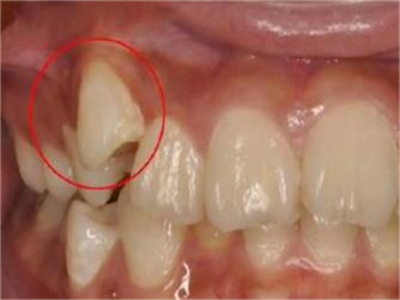

阻生牙可反复引起冠周炎,或引起邻牙牙根吸收和破坏,位置不正,不能完全萌出,好发部位是上、下颌第三磨牙。